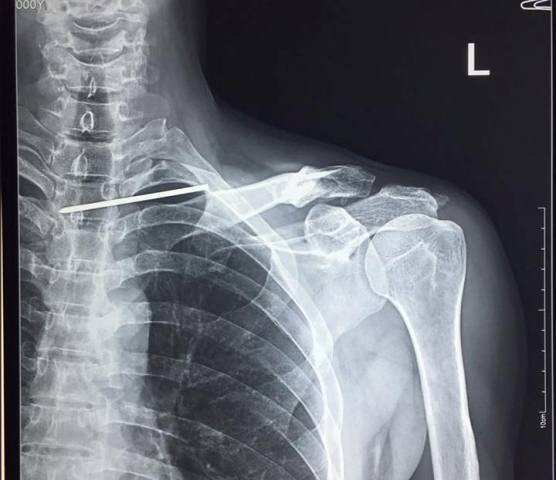

Hình ảnh X-quang chiếc đinh 12cm xuyên qua phổi và cắm vào tủy bệnh nhân T. (Ảnh BVCC)

BS. Trần Trung Kiên - Trưởng khoa Chấn thương chỉnh hình, BVĐK Đức Giang cho biết, trường hợp bệnh nhân này vô cùng hi hữu, bệnh nhân bị một chiếc đinh Kirschner (K-wire) dài 12cm di chuyển từ phần đầu ngoài xương đòn chạy xuyên qua đỉnh phổi xuyên thẳng vào tuỷ sống. Điều kì lạ là bệnh nhân không hề có bất cứ một dấu hiệu tổn thương thần kinh, vẫn sinh hoạt bình thường mà không hề hay biết về mức độ nguy hiểm của mình.